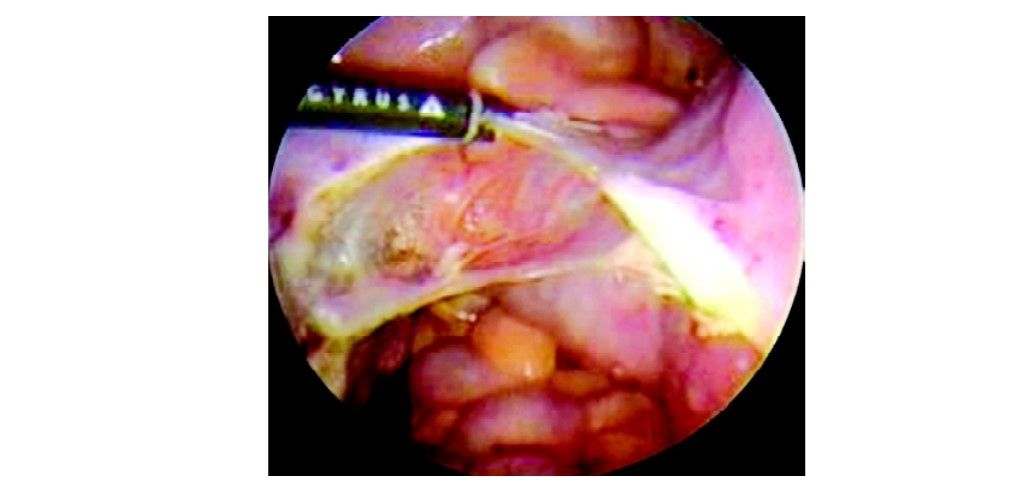

Laparoscopically assisted vaginal hysterectomy (LAVH) using bipolar

Successive desiccation and dissection